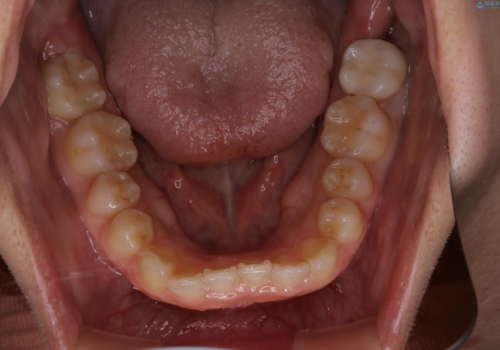

- 前歯が捻転していることを主訴に来院された方です。元々は部分矯正をご希望されていましたが、噛み合わせ等総合的に治療していくためインビザラインにて全顎的に治療を行うこととしました。

元々は上の前歯部の捻転のみの治療をご希望されていましたが、下の前歯もがたつきがあることや噛み合わせがかなり深いことを説明しました。後戻りのリスクを抑えるために全顎的な治療をご提案しました。

捻転していた上顎前歯部の仕上がりにこだわり、何度か修正を行ったため、満足のいく仕上がりになったと大変喜んでいただけました。